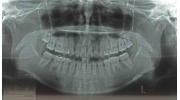

| 治療中